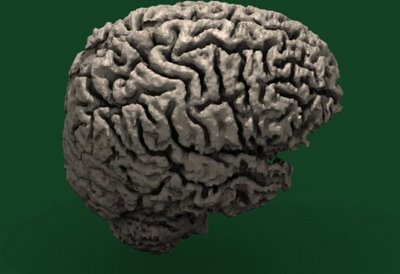

Human Brain!

Admit it: you did something wrong sometime in your life and someone told you: “Get a brain!” Well, now you can! A recent .STL upload to the Thingiverse model repository does just that. It’s a 3D model of an actual human brain! Now before you speculate on exactly *how* Jordan Miller obtained this anatomical… Continue reading Human Brain!